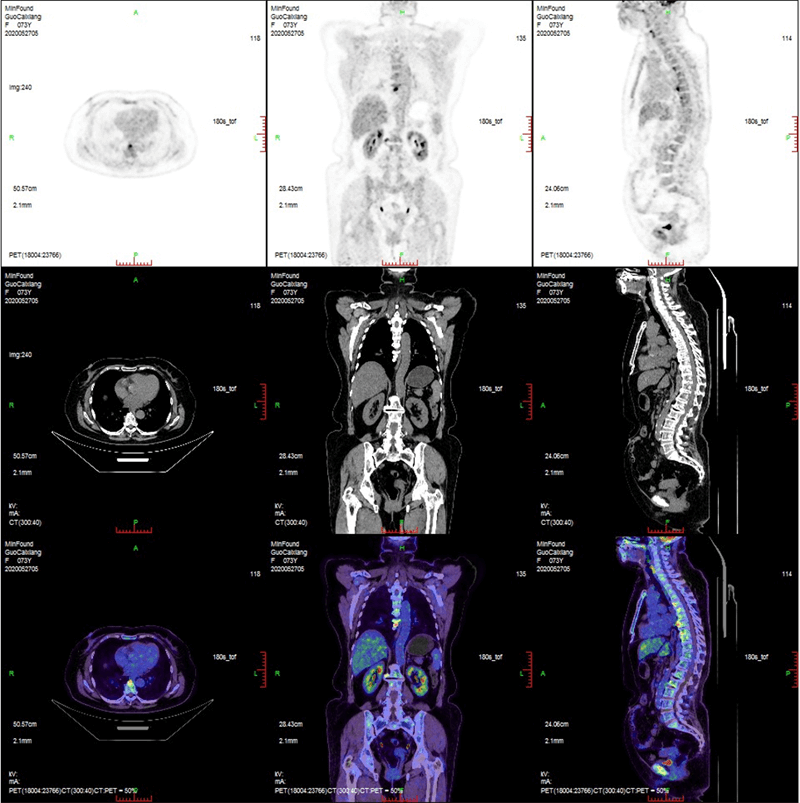

臨床畫廊